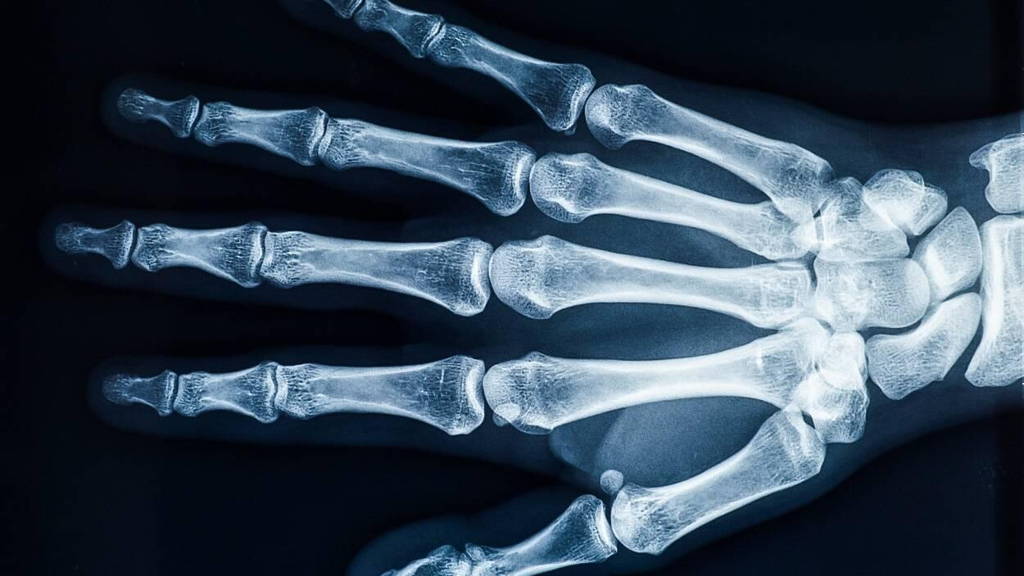

Wanneer een patiënt met een botbreuk op de huisartsenpost binnenkomt, kan de dienstdoende huisarts nu buiten kantooruren rechtstreeks diagnostiek aanvragen bij de afdeling radiologie van het CWZ. Dankzij de inzet van artificial intelligence (AI) van Gleamer BoneView, het programma dat de foto’s beoordeelt, hoeft de SEH-arts namelijk niet meer betrokken te worden bij de beoordeling van de foto’s. ’s Ochtends kijken de radiologen de beoordelingen wel nog na, om de kwaliteit te garanderen.

Effectieve analyse botbreuken

De effectiviteit van de applicatie BoneView is hoog, maar een dag later worden voor de veiligheid de resultaten wel nog gecontroleerd door radiologen. De slimme ondersteuning van BoneView wordt door betrokkenen als win-win-situatie omschreven voor medewerkers en patiënt. De slimme software is één van de vele AI aangedreven oplossingen die door GLEAMER zijn ontwikkeld om de patiëntenzorg en resultaten te helpen verbeteren. BoneView is door de FDA goedgekeurd voor het analyseren van (eventuele) botbreuken en buitengewoon betrouwbaar.